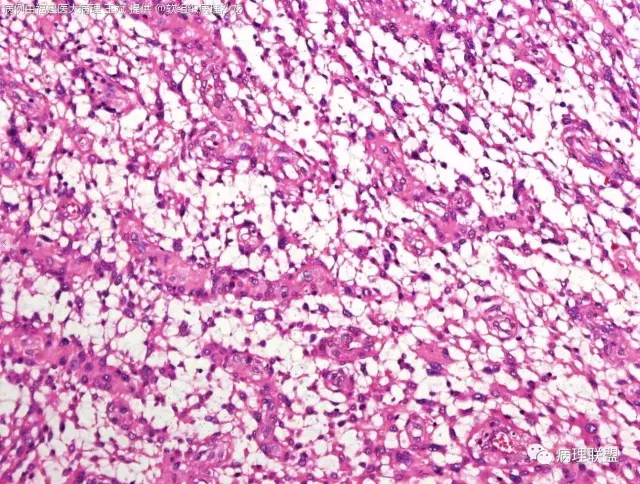

38岁,女性,手部小指背侧皮下肿物,3×2cm(病例由福建医大病理 王斌提供,致谢!)

血管瘤样纤维组织细胞瘤的肿瘤周围有淋巴细胞鞘,结节状分布,有假包膜,出血囊性变的为其主要特点,当然少数病例可以没有出血囊性变却出现粘液变。肿瘤细胞有一定异形性,属于低度恶性或交界性,最好做个FISH,看看有没有EWSR1-CREB1融合基因,刚查了一下,血管瘤样纤维组织细胞瘤还有另一种EWSR1-ATF1融合基因,无论是哪种,用EWSR1分离探针就可以检测